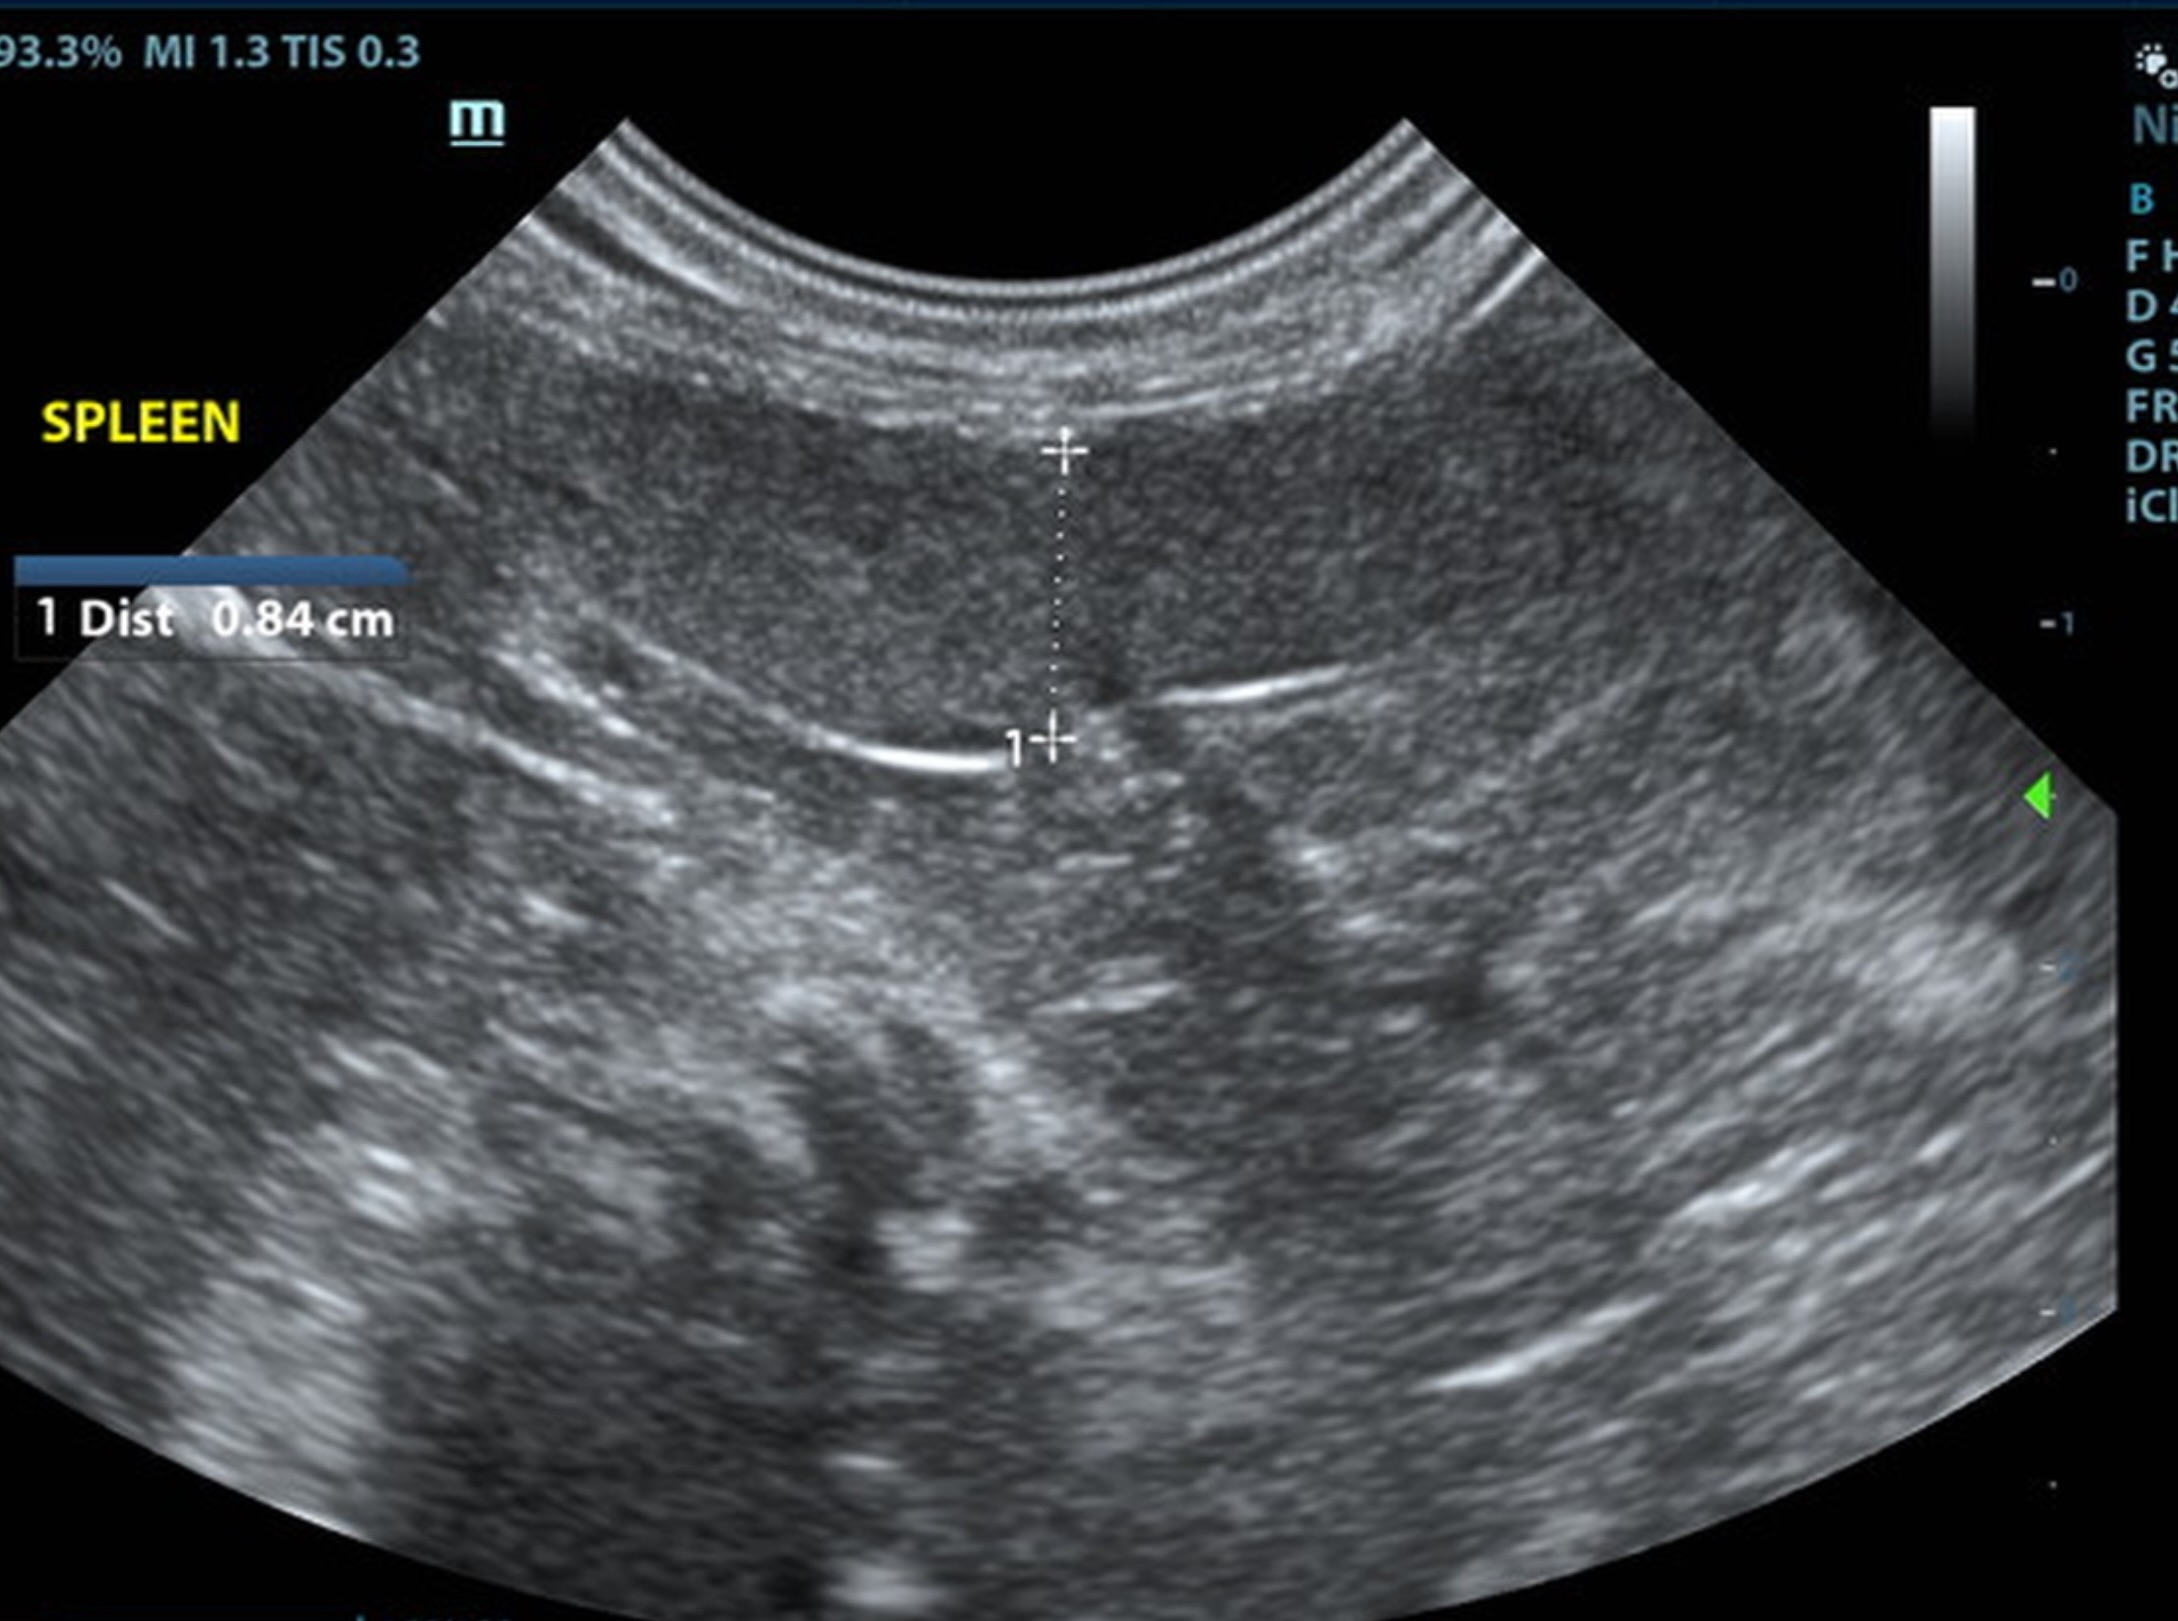

The spleen was mildly enlarged and folded upon itself caudally. The splenic parenchma was uniform. The spleen measured 0.84 cm.